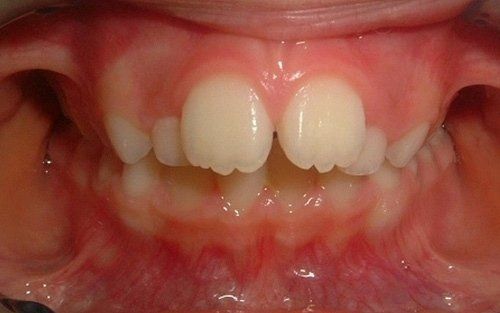

La "doppia fila" di denti: preoccupazione per i genitori

Una grande preoccupazione per i genitori è rappresentata dalla presenza contemporanea dei denti permanenti e dei denti da latte (che non cadono).Questa condizione non è affatto pericolosa per i denti permanenti, che prima o poi andranno a posizionarsi nella loro sede definitiva, dando l'ultima spinta ai dentini da latte, che cadranno definitivamente. Tranne rare accezioni, non vi è alcuna necessità di traumatizzare il bambino anticipando questo processo naturale con fastidiose estrazioni dentali.

Ecco un classico esempio di contemporaneità di denti da latte e denti permanenti. Questa situazione preoccupa sempre molto i genitori.